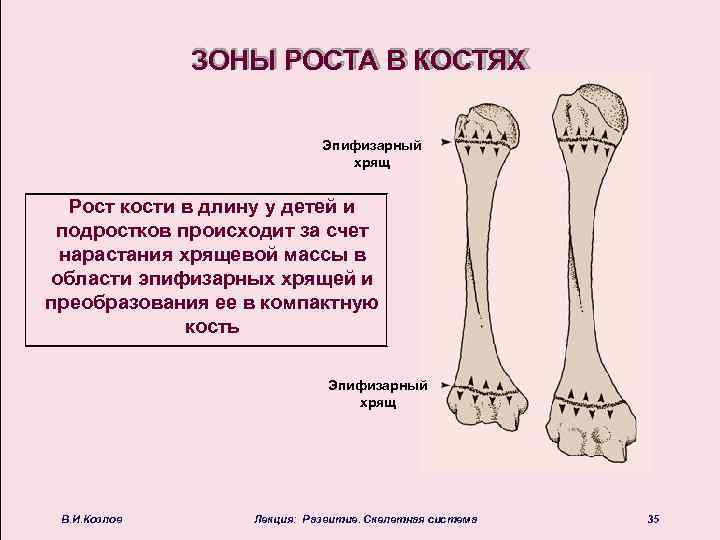

Локализация эпифизарных хрящей В. И. Козлов Лекция: Развитие. Скелетная система 34

ЗОНЫ РОСТА В КОСТЯХ Эпифизарный хрящ Рост кости в длину у детей и подростков происходит за счет нарастания хрящевой массы в области эпифизарных хрящей и преобразования ее в компактную кость Эпифизарный хрящ В. И. Козлов Лекция: Развитие. Скелетная система 35